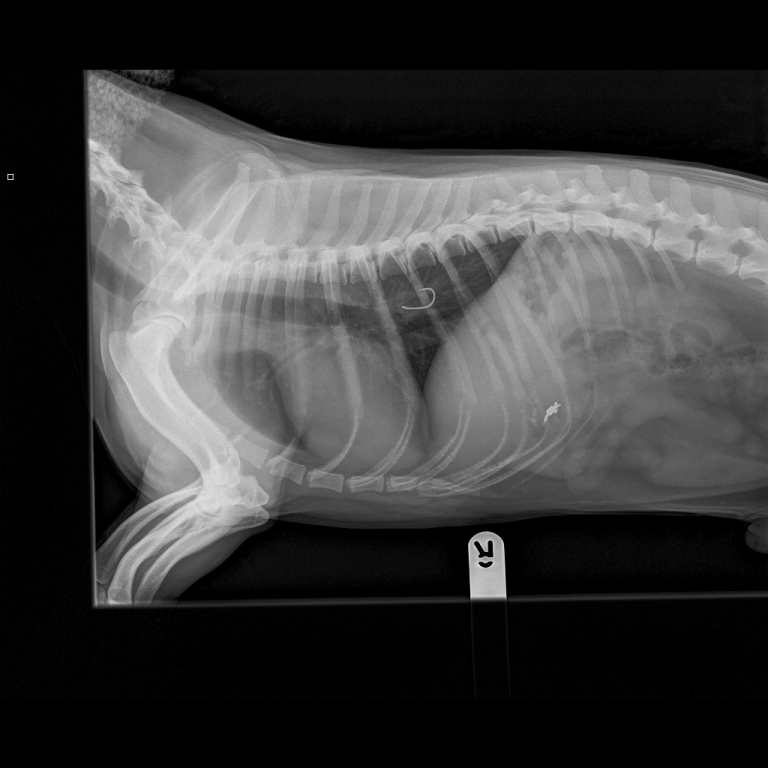

The large, double-barbed hook became lodged just below Marley’s heart, while the attached fishing line and weights continued down into the small intestine, creating a dangerous situation for the family pet.

“We took X-rays and performed an endoscopy to confirm the position of the hook and weights, and to examine where the hook had penetrated.